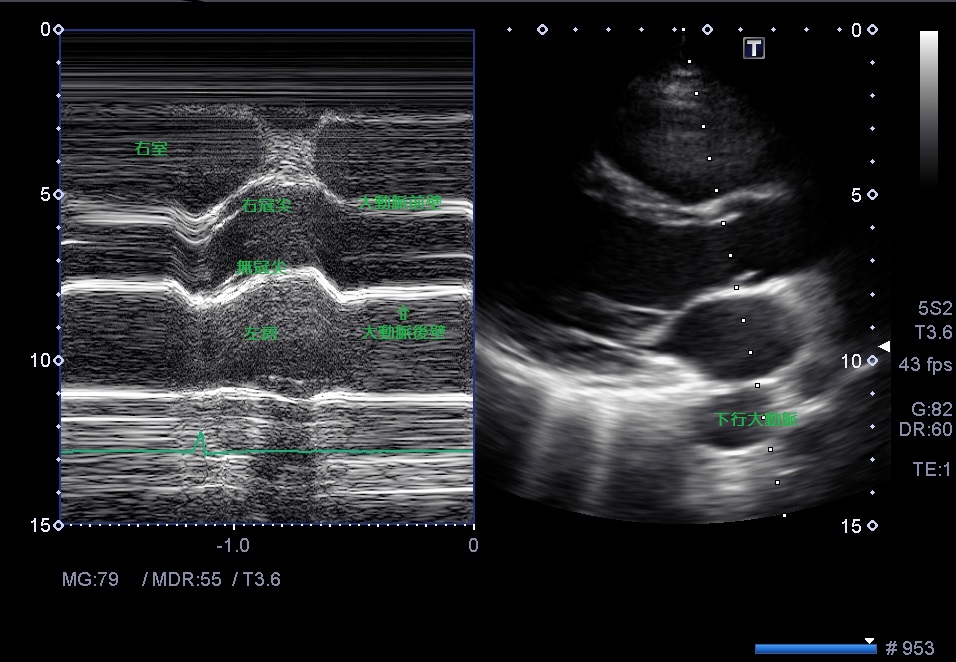

Mモード大動脈弁レベル

・大動脈弁基部を切る線で記録する

弁輪部にMモードのビームを合わせると、収縮期に右にずれてしまうのでややバルサルバ側に合わせる。

・腔に対して断面は垂直に入っているか?

・右室と大動脈と左房の大きさの関係は1:1:1

・大動脈弁の解放時に平行四辺形の線として描かれているか?box formation

・大動脈弁の開放径は1㎝以上あるか?1㎝未満だと弁の開放に障害がある。

Mモードの線が大動脈や左房の垂直に入ってないので少しプローブを右に倒す。

一肋間上からの描出を試してみる。

Mモードの大動脈前壁と大動脈後壁の動きが平行ではない